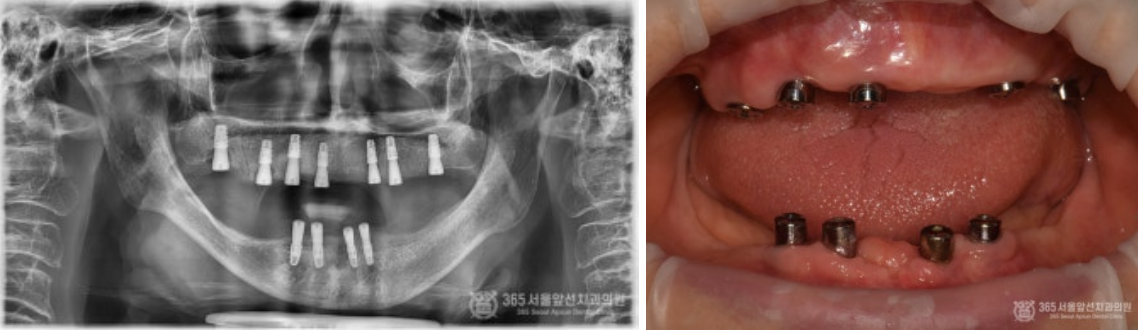

골다공증이 심해서 임플란트가 불가능하다는 이야기를 들었어요. 임플란트가 가능할까요? 상기 환자분은 골다공증으로 치료를 받고 계신 환자분이십니다. 골다공증제를 복용하고 계시거나, 골다공증 치료제 주사를 맞고 계실 경우 임플란트 치료시 고려되어야 하는 것은 널리 알려진 사실입니다. 결론부터 말씀드리자면 골다공증 치료를 받고 계시더라도 주치의와 상의해서 스케줄을 조율한다면 대부분 큰 무리 없이 임플란트 치료를 받으실 수 있습니다. 촬영일시 : 2024.07.05. 처음 내원 당시 엑스레이 사진입니다. 한눈에 보기에도 뼈가 거의 없어서 임플란트 치료가 쉽지 않으신 환자분입니다. 또한 엑스레이에서 보다시피 뼈의 밀도가 낮아서 뼈가 어둡게 보입니다. 골다공증 병력을 가진 환자분들에서 종종 나타나는 국소골다공성골수결손(Focal osteoporotic bone marrow defect) 양상을 보이셨던 환자분입니다. 촬영일시 : 2024.07.05. 임플란트 식립시 뼈의 모습입니다. 텅 빈 공간에 임플란트가 덩그러니 있는 듯한 모습이지만, 해당 공간은 임플란트를 식립하기 위해 뼈에 구멍을 낸것이 아니라 골수 결손으로 인해 원래부터 빈 공간이었던 부분입니다. 그 만큼 뼈의 상태가 매우 좋지 않았다는 것을 알 수 있습니다. 촬영일시 : 2024.07.05. 아래 앞니 부위도 뼈가 매우 얇아서 임플란트 식립시 뼈를 쪼개서 식립(ridge splitting)해야 할 정도로 매우 상태가 좋지 않았습니다. 촬영일시 : 2024.07.11. 수술이 잘 마무리된 후 엑스레이 사진 및 구강 내 사진입니다. 촬영일시 : 2024.11.11. 4개월 후 최종 보철물을 제작했습니다. 위턱은 전체임플란트로 치료를 마무리 지었고, 아래턱은 임플란트 브릿지와 틀니를 조합하여 잘 마무리해 드렸습니다~ ^^ 촬영일시 : 2024.07.05. / 2024.11.11. 구강 내 전후 비교사진입니다. 완전히 달라진 전후 모습을 비교할 수 있겠습니다. 오늘은 골다공증으로 인해 국소 골다공성 골수결손(focal osteoporotic bone marrow defect)이 발생된 환자분의 전체 임플란트 치료 증례를 소개해드렸습니다. 수 없이 많은 전체 임플란트 환자분들을 치료 하다보면 전신질환으로 인해 치료가 쉽지 않은 경우가 종종 있습니다. 하지만 질환을 잘 이해하고 있는 치과의사와 함께 한다면 치료를 잘 마무리 하실 수 있으니 걱정안하셔도 되겠습니다. 365서울앞선치과 대표원장 강동우였습니다. 감사합니다 ! [ 치료기간: 2024년 7월5일 ~2024년 11월 11일 ] ※ 365서울앞선치과의원의 모든 컬럼은 각 진료과 의료진이 직접 작성합니다. 365서울앞선치과의원 임상 케이스 게시물은 환자분께 의학적으로 정확하고 상세한 정보를 드리기 위해 각 진료과 의료진이 직접 작성하며, 모든 증례 사진은 본원 의료진이 직접 시술한 증례를 촬영한 것으로, 의료법 제23조, 제56조에 의거하며 환자분의 동의를 얻어 포스팅에 사용하였습니다. 또한 해당 케이스는 본 환자분의 치료 결과이며, 환자 상태에 따라 치료의 결과는 달라질 수 있습니다. |